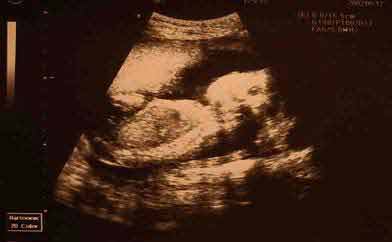

Most, a hatodik hónap végén érdekes visszaemlékezni az első három hónapra. Akkor még csak képeken láttuk, milyen is az, amikor a magzat növekedése szinte napról-napra nyomon követhető a kismama pocakterjedelmesedése által, s arról is csak olvashattunk, milyen döbbenetes élmény kívül-belül érezni mozgolódásait. Ezek mostanra mind valósággá lettek számunkra. Véget értek az émelygős hetek, a fáradtságot is mintha elfújta a szél, bár azért mégsem ugyanolyan az ember lánya már, mint lánykorában.

Ha nagyon koncentráltam, és még a lélegzetemet is visszafojtottam, már a 12. héttől éreztem bizonyos nagyon gyenge belső mozgolódásokat, de az igazi, semmi mással össze nem téveszthető hasba rúgás szeptember 17-én este ért. A legaktívabb időszak ezután is a reggeli és esti órák maradtak, de azért most, így a hatodik hónap vége felé közeledve egyre többször jelentkezik magzatunk napközben, sőt hajnalban is. A szürke novemberi reggeleken én még magamhoz sem tértem, Babó már intenzív nappali életet él.

ˇ Az ultrahangos vizsgálatnak vannak előnyei (korai méhen belüli várandósság, ill. halott magzat megállapítása, fogantatás napjának viszonylag pontos megállapítása, lágyrészdaganatok és elzáródások láthatók, a méhlepény helyzete megállapítható a 37.-38. héten) és hátrányai (a túl sok ultrahangos vizsgálat diszlexiát okozhat, a baba általában élénk mozgással, sokszor védekezéssel reagál, az ultrahangot mint zajforrást éli meg). Ennek tudatában érdemes dönteni arról, milyen gyakran vetjük alá magzatunkat ennek a beavatkozó vizsgálatnak. A tapasztalat azt mutatja, hogy a 32. heti utrahangvizsgálat alkalmával a babák nagy része farfekvéses helyzetben található, ami még gyakran változik. Erről tanúskodik a 37.-38. héten elvégzett vizsgálat. Ha ezt a kismamákkal is közölnék a 32. heti vizsgálatkor, megtakaríthatnának nekik néhány heti idegeskedést.